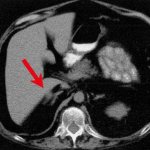

Однако не все так просто. Определенные фракции способны наносить существенный вред здоровью сосудов. При нарушении физиологического баланса липопротеидов различных классов твердое нерастворимое вещество способно откладываться на стенках артерий и капилляров, уменьшая их просвет и создавая серьезные препятствия для естественного кровотока.

Особенно опасно, когда известково подобные отложения концентрируются в сосудах, обеспечивающих кровоснабжение головы. Ведь недостаток поступления к ним крови – это риски ишемических проблем в зонах головного мозга с вероятностью развития инфаркта его жизненно важных структур.